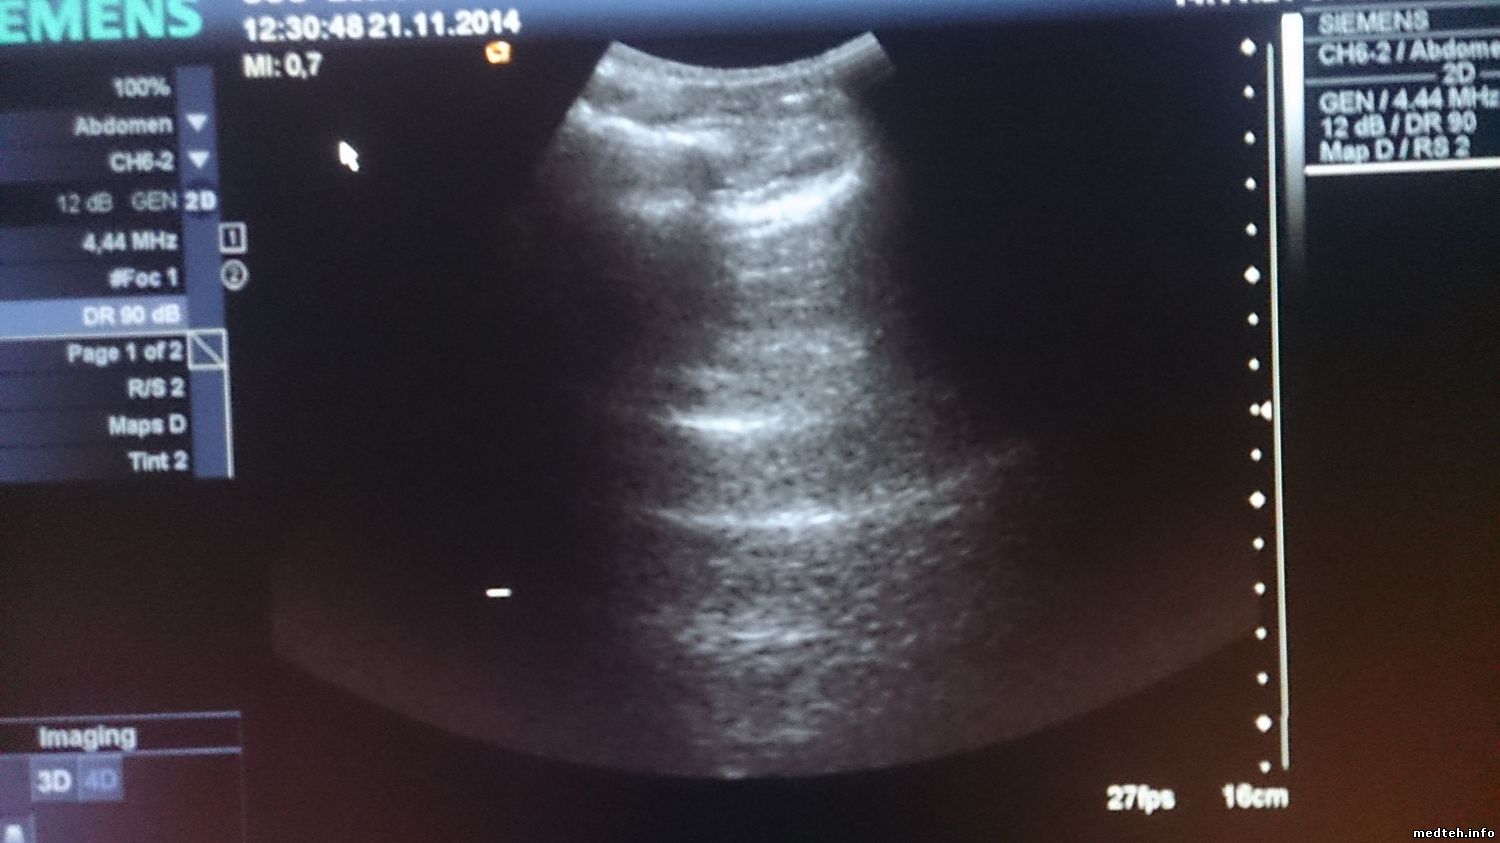

Сразу после включения качество более-менее (рис.1), хотя заметно, что изображение немного "восковое". К концу рабочего дня изображение ухудшается, повышается шум, изображение "плывет" (рис.2,3). На всех датчиках, хуже всего на фазированном. Появилось это давно. Аппарат ремонтировали по гарантии несколько лет назад, что-то меняли. Делали-ли tune-up, неизвестно. Пароля, естественно, нет. Как проконтролировать напряжения? Какие тесты можно сделать?